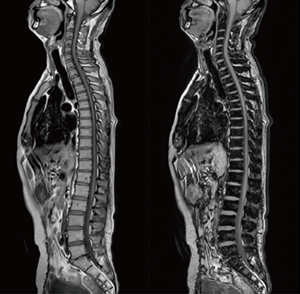

■症例2:膵がん/多発性肝転移

a:DWI(b=800) b:ADC

scan time:2:38,スライス厚:6mm,

マトリックス:108×124